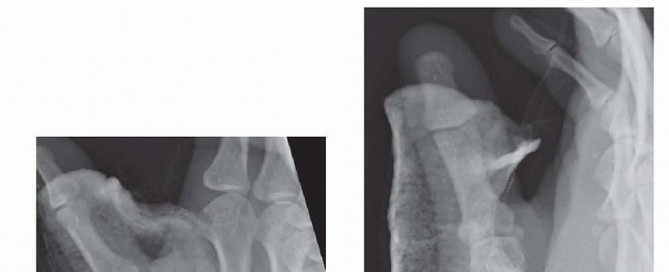

Fracture Patterns and Buchler Zones

These deforming forces lead to classic intra-articular fracture-dislocation patterns. The Bennett Fracture is a two-part intra-articular fracture where the metacarpal shaft is radially and dorsally displaced by the pull of the APL. Crucially, a small, intact ulnar fragment remains at the base of the thumb metacarpal, held perfectly reduced by the strong volar beak ligament. The Rolando Fracture represents a more complex, comminuted intra-articular fracture involving the base of the thumb metacarpal, classically presenting as a T or Y-type pattern. By definition, no portion of the metacarpal shaft remains in continuity with the CMC joint, rendering it profoundly unstable.

Image

Buchler et al. elegantly described three critical zones at the base of the thumb metacarpal, which guide our understanding of stability and operative indications. Zone 1 encompasses the volar aspect of the joint, typically involving the beak ligament avulsion. Zone 2 represents the central, normally loaded portion of the joint; involvement here is absolutely critical for load transfer and stability, almost universally mandating operative intervention. Zone 3 encompasses the dorsal aspect of the joint. Understanding these zones allows the surgeon to conceptualize the fracture in three dimensions and plan the trajectory of internal fixation devices accordingly.